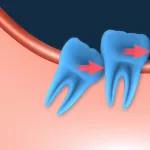

Além disso, a técnica previne a reabsorção óssea, mantendo a estrutura do osso e a estética do sorriso. Nossa equipe realiza uma análise detalhada de cada caso, assegurando que o paciente esteja apto para o método.

Outro ponto importante é a preservação do osso. A técnica evita a reabsorção óssea, mantendo a estrutura facial e garantindo resultados duradouros. Com um planejamento cuidadoso, o procedimento oferece segurança e eficiência.

Entre as complicações associadas à técnica, destacam-se infecções e a rejeição do implante. Pacientes com infecções ativas ou insuficiência óssea podem não ser indicados para esse método. A falta de osso suficiente pode comprometer a estabilidade do dente e aumentar os riscos de falha.

A carga imediata também se destaca pela estabilidade. A técnica promove uma integração óssea mais rápida e segura, preservando a estrutura do osso e garantindo resultados duradouros. Isso é especialmente importante para pacientes que desejam evitar a reabsorção óssea.